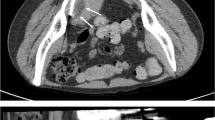

Its current use in the field of musculoskeletal disorders is mainly confined to the treatment of small joints and localized diseases, such as Morton’s neuroma (Fig. 2), and disorders involving the interapophyseal facets of the vertebral column [21] or the temporomandibular joint [20]. Its mechanism of action is not yet fully known, but it seems to be linked to the gas’s ability to reduce free radical production caused by intense mechanical stress [22]. This reduction produces an anti-inflammatory effect, which is the basis of ozone’s clinical effectiveness. Its effects are naturally limited in large part to pain relief [21]; its ability to improve functional impairment is restricted to the pain-dependent component.

Morton’s neuroma. Axial STIR T2-weighted MRI scan. The neuroma is clearly visualized in the space between the third and fourth metatarsals (a). Scan performed along the short axis of the nerve with a high-frequency linear transducer. The neuroma is clearly visualized as a hypoechoic lesion located in the space between the metatarsal heads (b). The needle tip is inserted into the neuroma (c). After treatment, the neuroma appears hyperechoic (d)